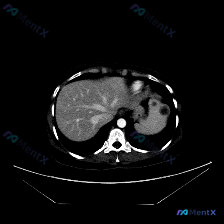

单张上腹部CT横断面(软组织窗):

- 肝脏、腹主动脉、下腔静脉等周围结构大致正常

- 脾脏实质内见数个类圆形低密度灶,边界相对清晰

- 无明显渗出、炎症或肿大淋巴结等其他伴随征象